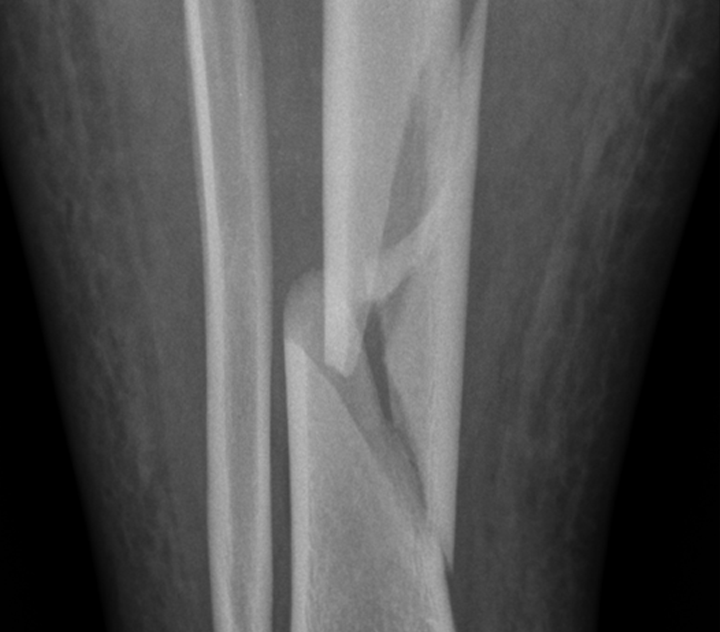

Röntgenaufnahme des Unterschenkels bei komplexer Fraktur von Scheinbein und Wadenbein.